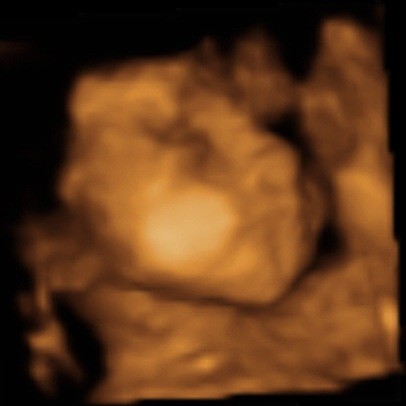

ślicznyNie wiem, ktory temat odpowiedni, wiec wstawie fotki naszego synka tutaj (nie sa to medyczne skany, wiec watek lekarski chyba nie pasuje, nie sa to tez zdjecia brzuszka...)

Zobacz załącznik 435458